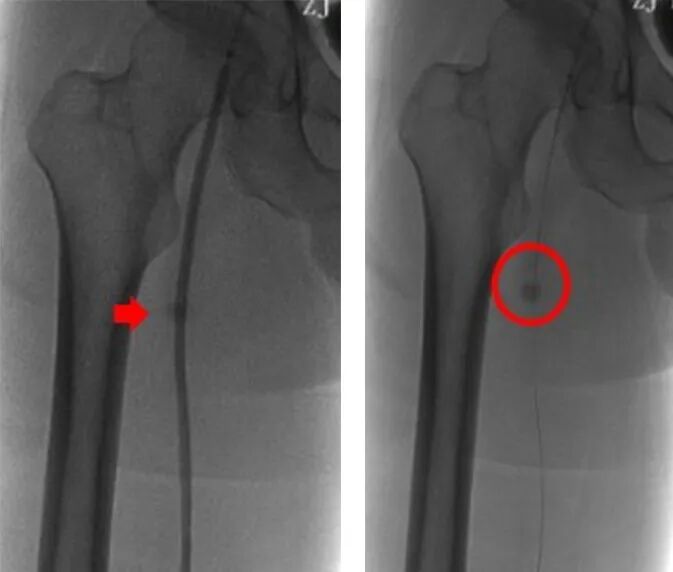

5、0.1%利多卡因局麻下切开股浅动脉近端病变,探查见股浅动脉病变类型为慢性动脉硬化闭塞合并血栓形成,同时可见局限性股浅动脉瘤样扩张。

6、术中对于血栓组织予以直视下取栓,股浅动脉近端分叉病变予以内膜剥脱成形,股浅动脉远端病变予以置入Smart裸支架6*150mm、6*100mm,对于股浅动脉瘤予以缩窄缝合并将支架近端超过瘤样病变至少1cm,并予以5*150mm球囊后扩支架。

7、最后造影显示右股腘动脉显影通畅,支架形态良好,膝下胫前动脉显影通畅,未见明显造影剂滞留现象,遂撤出导丝导管,左腹股沟穿刺处予以置入Exoseal封堵器封堵穿刺点后,予以加压包扎。

8、患者术后一周康复出院,出院前复查ABI右侧0.78(较术前0.40明显提升),出院带药:双通道抗凝及抗血小板治疗(阿司匹林肠溶片100mg 联合利伐沙班片10mg )。

术后1年随访结果:右下肢血管B超提示右股浅动脉支架内尚通畅,患者继续门诊随访中。